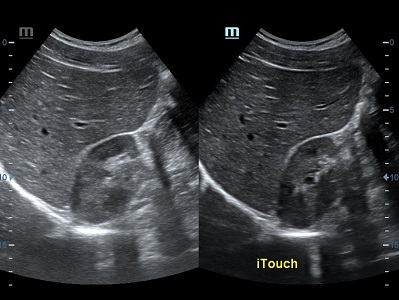

Оптимизация изображения происходит и за счет постобработки. Наиболее часто используемый инструмент - общее усиление (Gain). Усиление делает изображение «ярче», но чем сильнее усиление, тем меньше различия между структурами. Также используются усиление по времени (TGC) и усиление по длине (LGC), которые позволяют изменять отображение на экране послойно, позволяя подсветить гипоэхогенные участки, или, наоборот, снизить визуально эхогенность слишком ярких моментов. Данный вид оптимизации требует много времени, для упрощения работы доктора на приборах Mindray внедрена система автоматической оптимизации - iTouch.